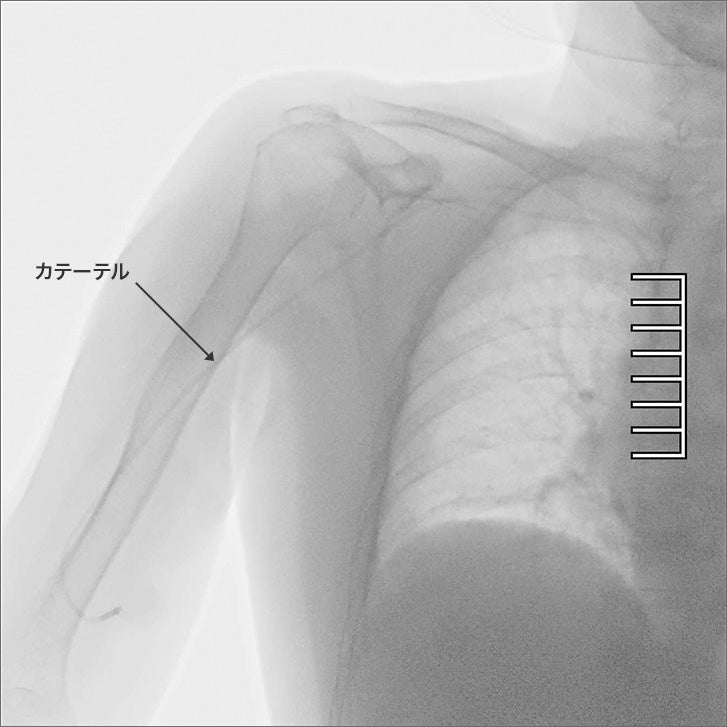

通常では見ることが難しかった部分のカテーテルも鮮明に観察可能

X線を用いた撮影装置で、レントゲンのように静止画を撮影するのではなく、リアルタイムの動画で体の中を透視・撮影する装置です。造影剤などを使用することで、血管や臓器が造影される様子を確認しながら撮影することも可能です。主に消化器科や整形外科での検査などで使用されるほか、内視鏡やカテーテルなどの進化により、検査だけではなく治療で使用される機会も増え、幅広い診療科で活用が広がっています。